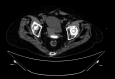

Results: Five patients (2 male, age 44-89 years) were included. Four patients had postoperative PFCs, and 1 presented with a pelvic abscess complicating acute diverticulitis. Two of 5 had fecal diversion; the remaining 3 had unaltered large-bowel anatomy. One case had a concomitant abdominal collection, treated with percutaneous drainage in the same session. An electrocautery-enhanced LAMS delivery system (15 × 10 mm) was used in all cases. EUS-TRD was performed with the direct-puncture technique and lasted less than 10 minutes in 4 cases; in the remaining case, needle puncture and LAMS placement over a guidewire was required, and the procedure length was 14 minutes. The clinical success rate was 100%. LAMSs were removed after a median of 14 (range, 12-24) days. One patient reported partial proximal LAMS migration after 24 days (mild adverse event). No PFC recurrence was observed.